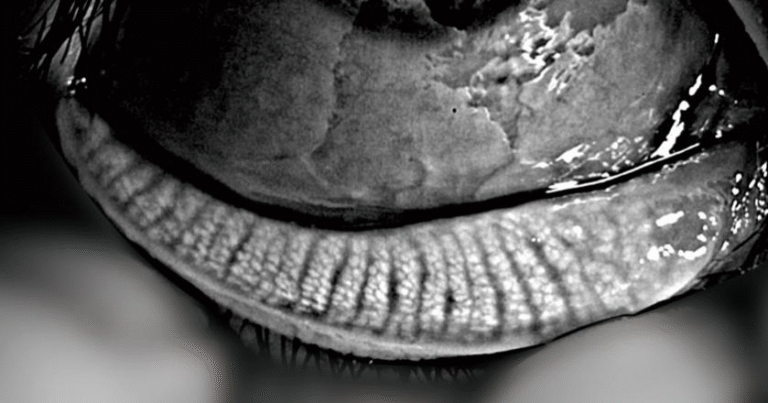

Dry Eye

Full ocular surface analysis

Advanced Dry Eye analysis

Built-in Digital Analysis